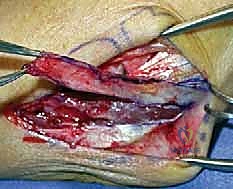

التدخل الجراحي: المعيار الذهبي

بالنسبة للغالبية العظمى من المرضى النشطين، والشباب، والرياضيين، تعتبر الجراحة هي الحل الجذري والوحيد لاستعادة استقرار الكوع ومنع التآكل الغضروفي المبكر (الخشونة). نظراً لأن الأربطة الممزقة بشكل مزمن تضمر وتفقد جودتها، فإن مجرد خياطتها (الإصلاح المباشر) غالباً ما يبوء بالفشل. لذلك، فإن الإجراء المفضل عالمياً والذي يبرع فيه الأستاذ الدكتور محمد هطيف هو إعادة بناء الرباط (Reconstruction) باستخدام رقعة وترية.